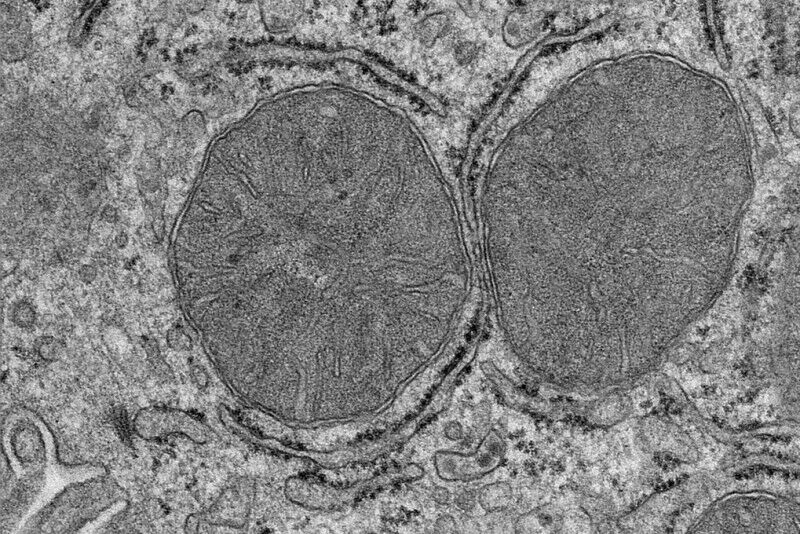

Elektronenmikroskopische Aufnahme der Mitochondrien in Leberzellen. Die Mitochondrien verändern ihre Form, sobald Nahrung wahrgenommen wird. © MPI f. Stoffwechselforschung/ S. Henschke

Was passiert im Körper, wenn wir hungrig sind und Essen sehen und riechen? Ein Forschungsteam des Max-Planck-Instituts für Stoffwechselforschung in Köln konnte jetzt an Mäusen zeigen, dass bereits nach wenigen Minuten Anpassungen in Mitochondrien in der Leber stattfinden. Angeregt durch die Aktivierung einer Gruppe von Nervenzellen im Gehirn, verändern sich die Mitochondrien der Leberzellen und bereiten die Leber auf die Anpassung des Zuckerstoffwechsels vor. Die Ergebnisse könnten neue Wege für die Behandlung der Volkskrankheit Typ-2-Diabetes eröffnen.

Wenn hungrige Mäuse Futter angeboten bekommen, dieses aber nicht essen, sondern nur sehen und riechen können, werden nach nur wenigen Minuten in den Mitochondrien der Leber Prozesse aktiviert werden, die normalerweise durch die Nahrungsaufnahme angeregt werden. Den Untersuchungen der Kölner Forschenden zufolge reicht dies aus, um die Mitochondrien in den Leberzellen zu verändern. Dies wird durch eine bisher nicht charakterisierte Phosphorylierung in einem Protein der Mitochondrien vermittelt. Die Phosphorylierung ist eine wichtige Modifikation für die Regulation der Proteinaktivität.

Die Wirkung auf die Leber vermittelt eine Gruppe von Nervenzellen, die so genannten POMC-Neuronen. Diese Neuronen werden durch den Geruch und Anblick von Nahrung innerhalb von Sekunden aktiviert und signalisieren der Leber, sich auf die ankommenden Nährstoffe vorzubereiten. Die Forschenden konnten auch zeigen, dass allein die Aktivierung der POMC-Neuronen ausreicht, um Mitochondrien in der Leber anzupassen, selbst wenn keine Nahrung da ist. ,,Wenn unsere Sinne Essen wahrnehmen, bereitet sich unser Körper mit einer Produktion an Speichel und Magensäure auf die Essenaufnahme vor. Aus früheren Untersuchungen wussten wir, dass sich auch die Leber auf die Nahrungsaufnahme vorbereitet. Jetzt haben wir uns die Mitochondrien in den Leberzellen genauer angesehen, weil sie essentielle Zellorganellen für den Stoffwechsel und die Energieproduktion sind und festgestellt, wie Überraschend schnell diese Adaption abläuft", erklärt Sinika Henschke, Erstautorin der Studie.